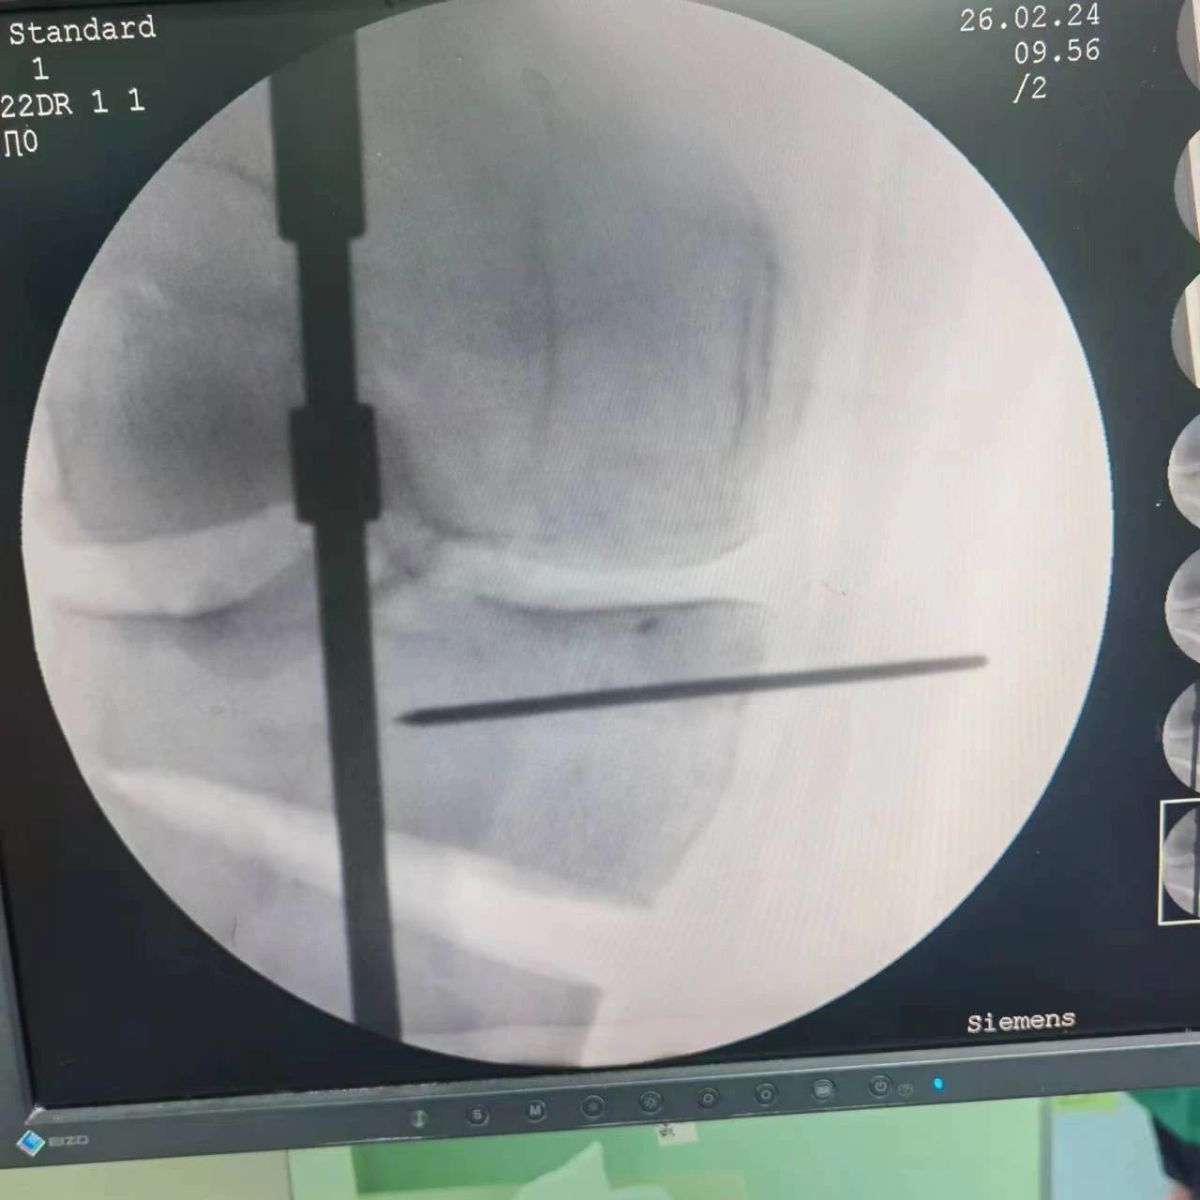

2月26日,漯河市骨科醫(yī)院(漯河醫(yī)專二附院、漯河市立醫(yī)院)膝關(guān)節(jié)外科、運動損傷科(骨六科)在保膝治療方面取得了新的突破,李付彬主任帶領(lǐng)岳龍等團(tuán)隊醫(yī)師,順利完成“計算機(jī)精準(zhǔn)術(shù)前規(guī)劃聯(lián)合3D打印截骨導(dǎo)板輔助脛骨高位截骨治療膝關(guān)節(jié)骨性關(guān)節(jié)炎”的手術(shù),這在漯河市尚屬首例!

李付彬主任團(tuán)隊通過精準(zhǔn)術(shù)前規(guī)劃,設(shè)計目標(biāo)力線及調(diào)整撐開角度,轉(zhuǎn)化成需要撐開的高度,最終設(shè)計出同等高度的填充塊,術(shù)中驗證力線調(diào)整與術(shù)前規(guī)劃完全一致!

鋼板位置、螺釘位置及長度均可通過術(shù)前規(guī)劃計算,術(shù)中通過定位操作,基本與術(shù)前規(guī)劃一致,手術(shù)快速高效完成,外側(cè)合頁保留完整。無任何并發(fā)癥出現(xiàn)。術(shù)后見鋼板位置及力線糾正近乎完美!

OWHTO手術(shù)效果依賴于多個數(shù)據(jù)參數(shù),比如:截骨的入點、合頁位置的選擇、截骨線的深度、截骨線的方向、撐開的距離等,依托計算機(jī)術(shù)前精準(zhǔn)規(guī)劃和3D打印導(dǎo)板可輔助醫(yī)生精準(zhǔn)控制上述參數(shù),使截骨更準(zhǔn)確,真正達(dá)到精確的力線調(diào)整,減少術(shù)中透視次數(shù),縮短手術(shù)時間并降低手術(shù)風(fēng)險,從而使得OWHTO得到更好的應(yīng)用,造福患者。